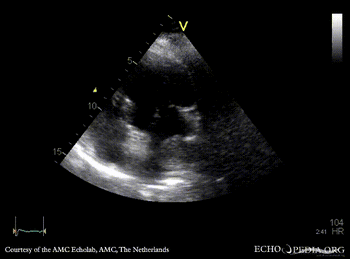

| PSAX: tumor mass in left atrium | A4CH |

| A4CH, zoom | |